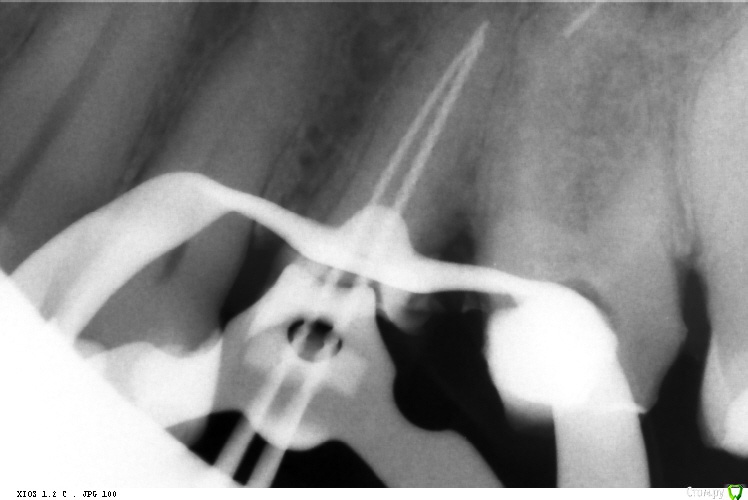

St. Опубликовано 23 марта, 2016 Автор Поделиться Опубликовано 23 марта, 2016 Эх, что-то сезон косяков. Аж руки опускаются... Видимо пора в отпуск. 36 пульпит. Запаковала по апексу -0,5. Что получилось - снимок 2. Попросили перепаковать. В итоге по апексу в 0, плюс 1,5 часа времени 1 Ссылка на комментарий